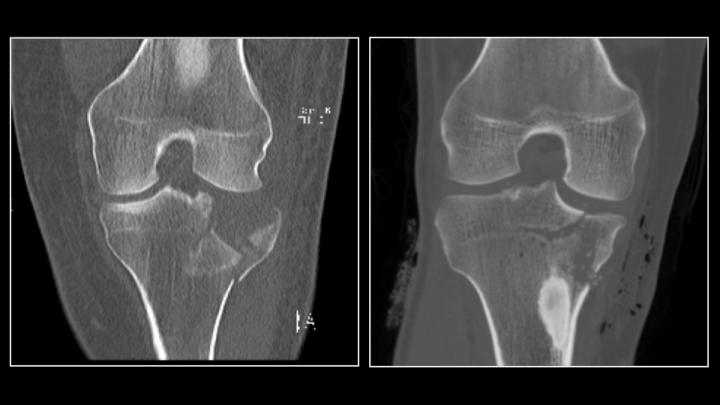

(ORLANDO, Fla.) Computed Tomography (CT) scans are one of the most frequently-used imaging tools in medicine. In fact, more than 72 million scans are performed each year to diagnose various medical conditions. But public health concerns persist about radiation exposure from these tests -- especially when given to children and young adults. Now, researchers at NYU Langone Medical Center report in a new study that they successfully performed CT scans for joint fractures with one-fourteenth the amount of normal CT radiation -- without compromising image quality or a surgeon's ability to effectively diagnose an injury.

Specifically, the researchers reduced the average amount of radiation from 0.43 msV to 0.03 msV, or down to the average dose given in a routine chest x-ray. Equally important, the researchers were able to accurately identify the presence of typical fractures 98 percent of the time.

In orthopaedic trauma, CT scans help diagnose injuries around a joint, particularly if the fracture involves the joint's surface. The scans also help clinicians assess joint displacement and aid in surgical planning to put the joint back in position. An X-ray, while a good initial screening tool, does not provide the same level of detail.

Between August 2014 and March 2015, 50 patients showing clinical symptoms of joint fractures received ultra-low dose radiation CT scans. Images from these ultra-low dose CT scans were compared to a sample of age-matched, similar fracture injuries where patients were evaluated with a standard CT scan.

The results were impressive: researchers achieved 98-percent sensitivity and 89 percent specificity with the ultra-low dose CT scans. In other words, if a person has a joint fracture, it would be detected on the ultra-low dose CT scan 98 percent of the time, while a negative finding - no fracture having occurred -- was determined 89 percent of the time. Equally important, these findings were comparable to the conventional CT-scans (98 percent sensitivity and 85 percent specificity with occult fractures removed). Image quality was rated moderate to near perfect by the orthopaedic surgeons.